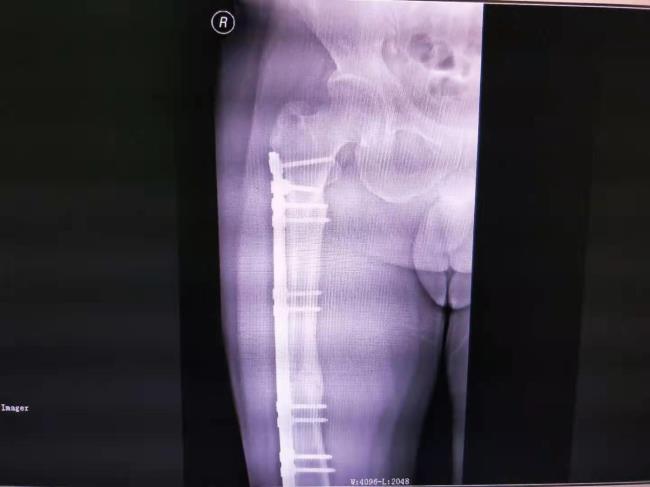

中医药结合桥接系统生物内固定技术

中医药结合桥接系统生物内固定技术治疗四肢骨折固定牢固,骨折愈合快,能早期康复,获广西医药卫生事宜技术推广奖三等奖。

病例1、右股骨多段粉碎性骨折治前及治疗后X线片